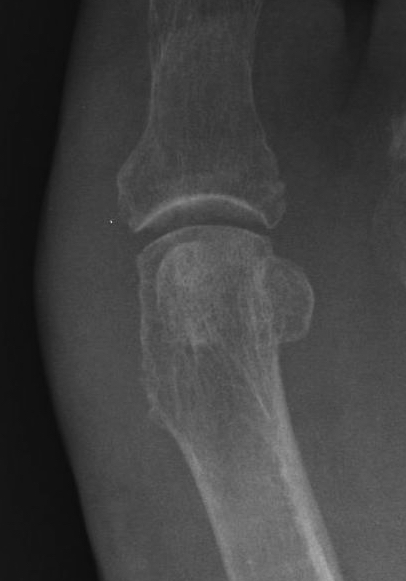

AVN

Management - arthrodesis